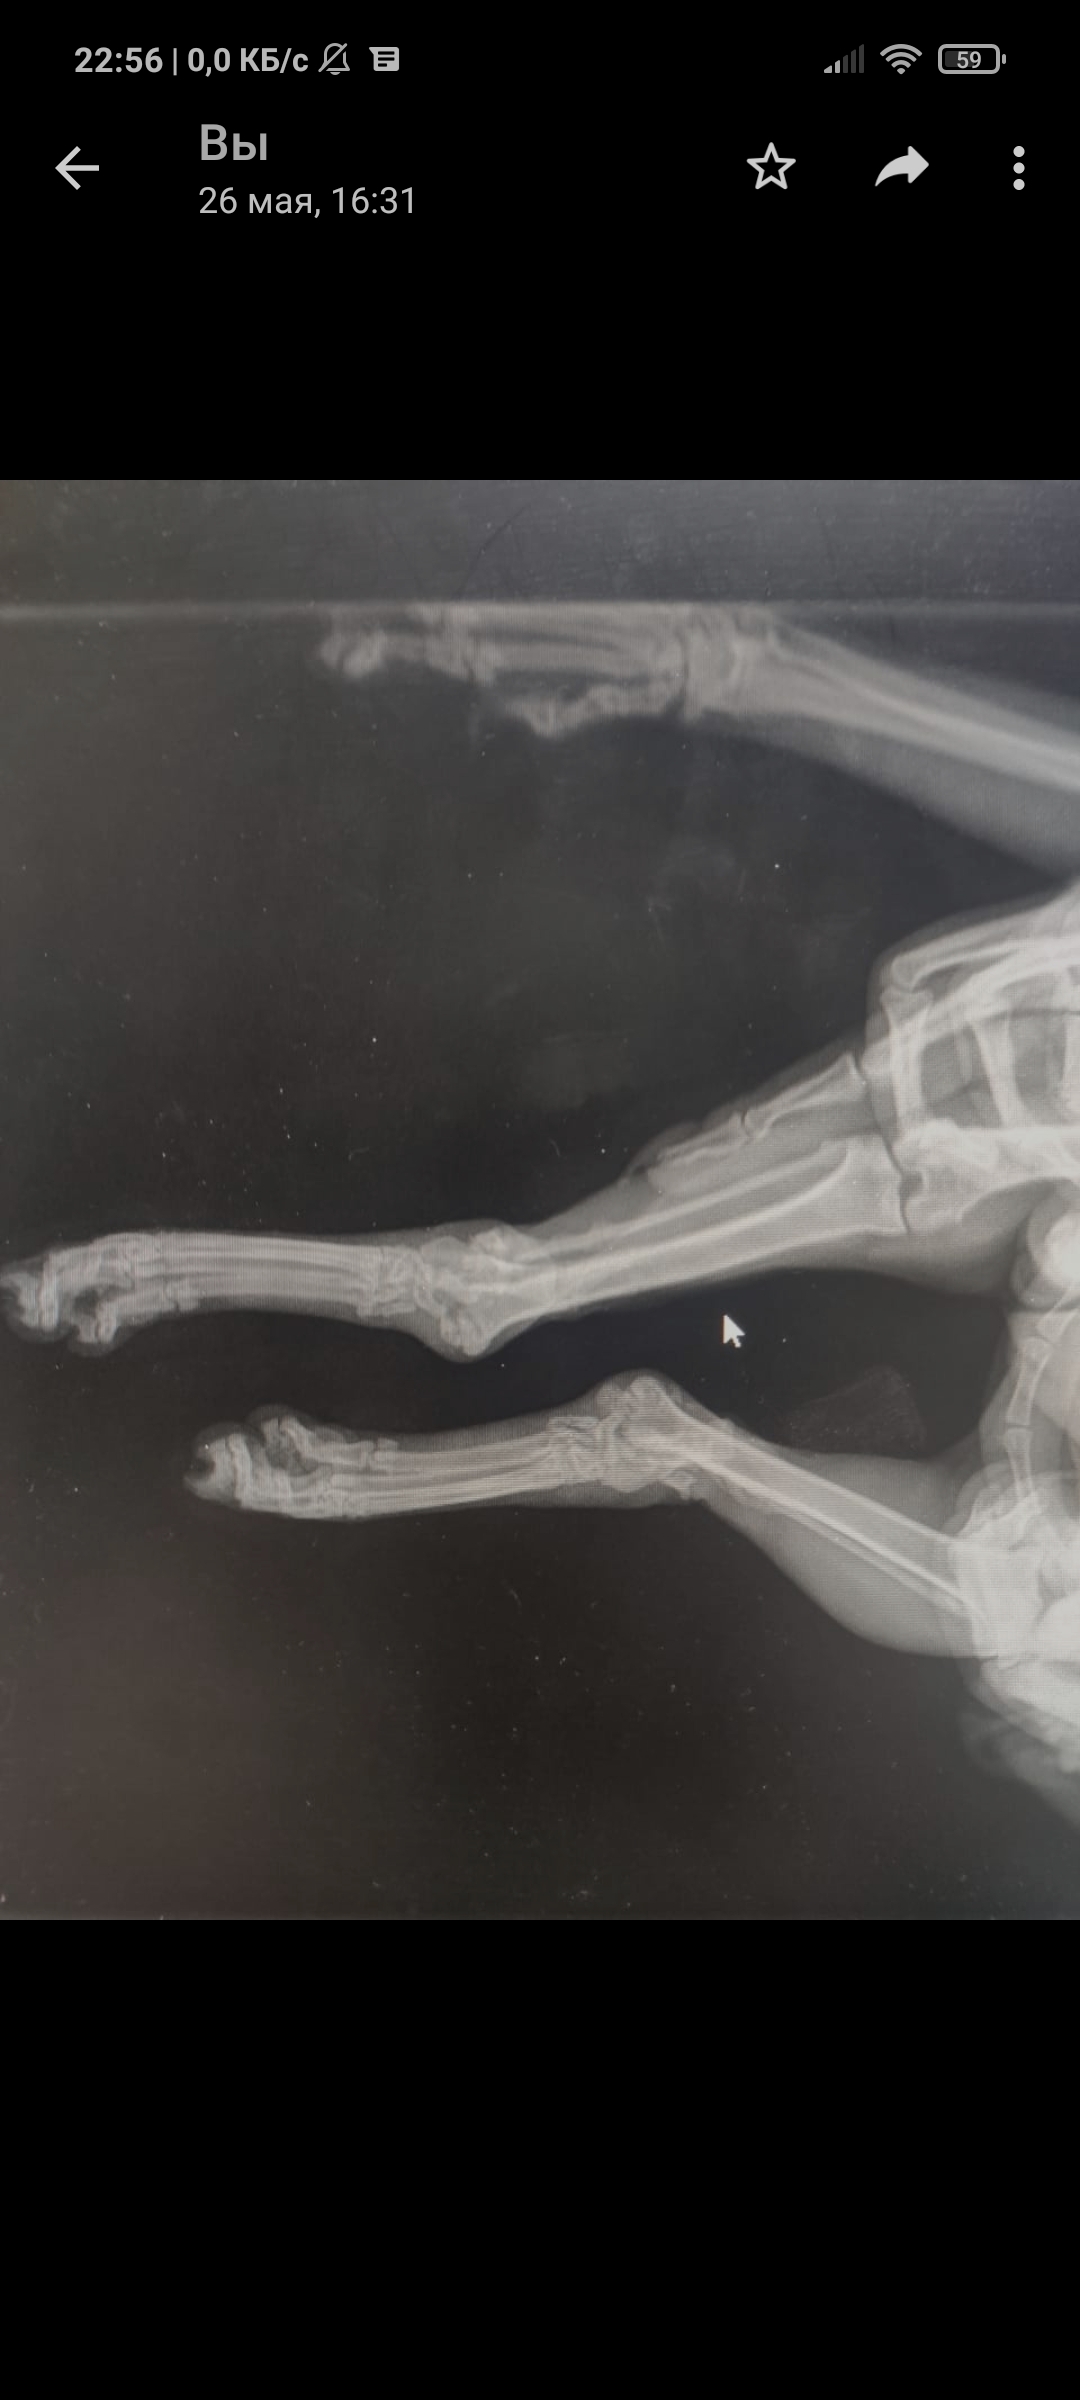

Так уж получилось что я ветеринарный врач, работаю в интенсивной терапии - принимаю и лечу самых тяжелых животных. На днях ближе к ночи прибегает женщина с котом, который шлёпнулся перед ней на улице. При осмотре выясняется что кот в шоке - лежит на боку, без давления, температуры, у него сломаны передние лапы, лицо, пневмоторакс и немного жидкости в брюшной полости (вероятно кровь). Женщина оставляет двадцатку на первые сутки и идет искать хозяина, кот помещается в стационар для стабилизации состояния. Всю ночь я ебусь с этим котом, вывожу его из шока, спускаю ему пневмоторакс, грею, обезболы льются рекой, к утру кот похож на кота, а не на покойника - начал садиться, ползать, полизал еду.

В общем, четвертый день от падения, полет нормальный, кот начал есть сам, а я иду на смену, ждите новостей, думаю скоро будет пост про то, как мы оперируем животных, в частности собираем ходули герою этой истории 😁